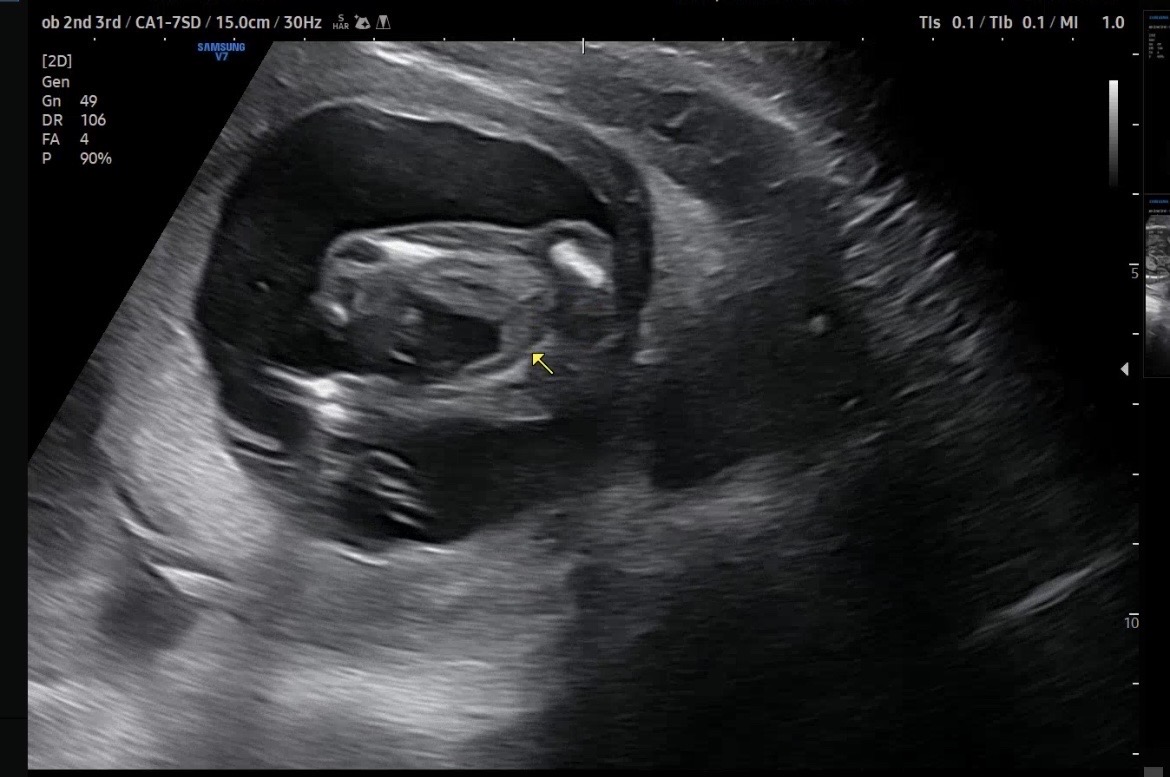

16주 성별 확정일까요! 함께 봐주세욘!

오늘 딱 16주 검진 받고왔는데요! 의사쌤이 확답을 안해주셔서… 매끈하긴한디… 딸 확정일까요..? 혹시 반전 이있을지 궁금합니다!

딸같아요

완전 딸이요!!!

딸맞네요 ㅎㅎ